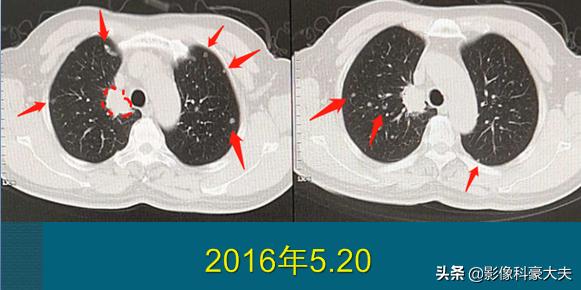

豪大夫不是吹牛,很多晚期肺癌病人都在创造和延续奇迹!今天还有一位复查的病人,3年半前确诊为肺癌晚期,双肺一百多个转移瘤和多发骨转移:

这位病人67岁,男性,因为咳嗽、胸痛做肺部CT,右上肺癌3.1cm,边缘有毛刺。因为肿瘤贴近胸膜,癌细胞沿着胸膜脉管系统(主要是淋巴系统)快速播散,像种子一样在双肺生根发芽,长出100多个转移瘤,还有胸椎、肋骨的多发骨转移,已经无法手术。

后来穿刺证实为低分化肺腺癌,基因检测阳性。他采用靶向治疗为主的综合治疗,吃了两年吉非替尼,定期服用双膦酸盐药物控制骨转移,辅助应用一下调理免疫的药物,从今年开始更换新的靶向药物,目前控制比较理想: